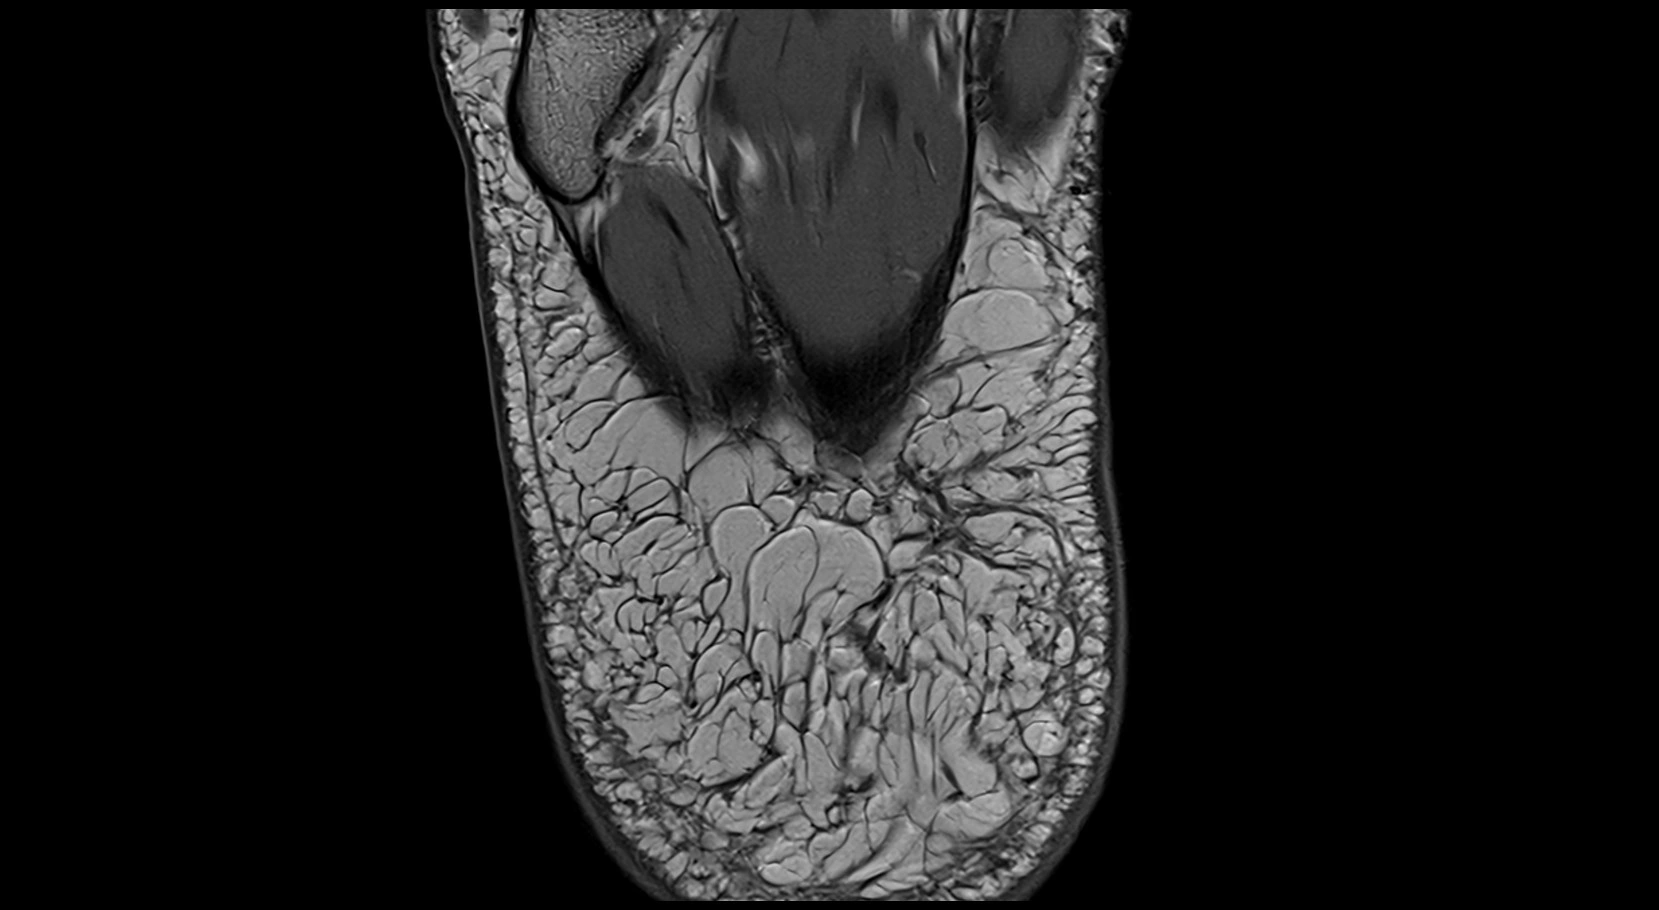

MRI image

image